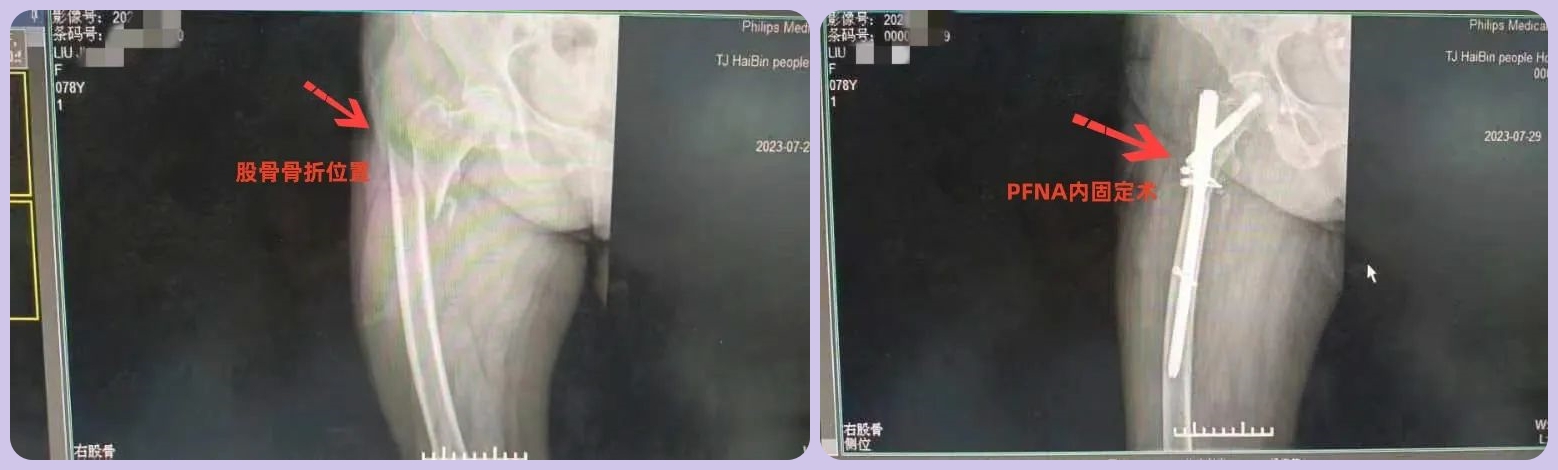

患者活动时不慎摔倒,检查确诊为右股骨骨折。经过全面检查、评估,结合老人身体情况,骨科团队建议行骨折切开复位髓内针(PFNA)内固定术。征求家属同意后,邀请天津医院专家指导完成手术。

在双方专家的共同努力下,手术过程顺利,骨折达到解剖复位,固定良好,取得了理想的效果。目前,老人在医生指导下开始康复锻炼,为后期恢复自主行走打下基础。

据悉,PFNA手术是一种新型股骨近端内固定系统,具有加压和抗旋转两种作用。手术切口小、出血少,对骨折断端血供干扰小,有利于术后愈合,能早期进行功能锻炼。骨科郭主任介绍说:该术式因其较高的稳定性和较强的把持力优势,目前已被应用于老年不稳定型股骨粗隆间骨折治疗中。海滨人民医院骨科也将加强与上级医院的沟通,通过邀请专家会诊、指导手术等形式,让该技术在医院落地,为南部城区老人诊疗提供更好选择。